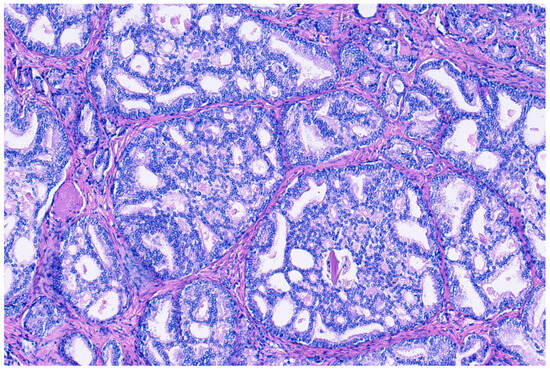

3. Cribriform Prostate Cancer

4. Differential Diagnoses